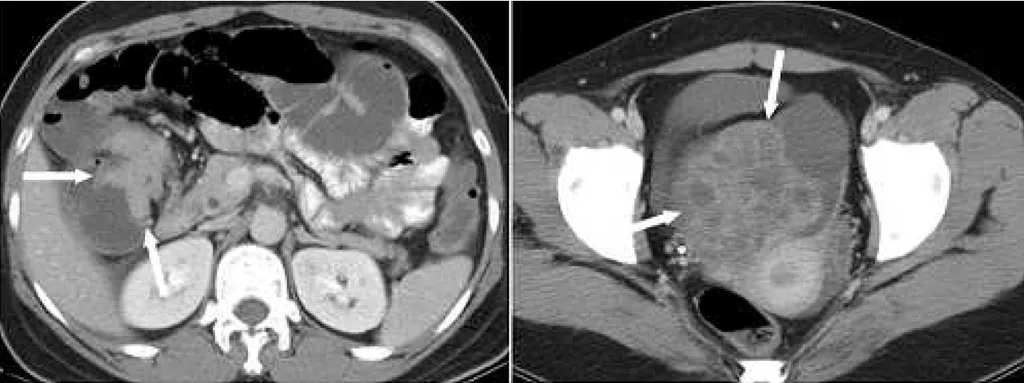

【113-1 醫學(六) 第74題】37 歲女性病人經電腦斷層檢查,發現影像中箭號所指處有結腸肝彎處腫瘤阻塞,合併右側卵巢多囊性腫瘤,下列有關卵巢的診斷何者最恰當?

詳解

破題關鍵

這題的解題核心在於「結腸肝彎處腫瘤阻塞」合併「右側卵巢多囊性腫瘤」,當消化道原發腫瘤與卵巢腫瘤同時出現時,要高度懷疑卵巢腫瘤是轉移性的,尤其是Krukenberg tumor。圖片中左右兩張CT影像分別清楚顯示了腸道腫瘤和卵巢腫瘤。

選項拆解